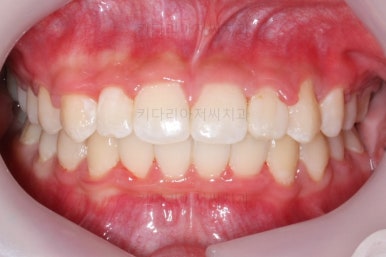

마무리 때의 모습입니다.

치아는 매우 가지런해졌고 뾰족하던 앞니의 형태도 좋아졌어요.

매복되어 있던 송곳니도 잘 나왔고 과개교합도 물론 개선이 되었습니다.

대신 웃거나 말하는 모습에서 드러나는 치열은 매우 예뻐졌어요.

부산교정치과 키다리아저씨치과에서 치료한 이번 치료의 전후사진을 비교해 볼게요.

왼쪽이 치료 전, 오른쪽이 치료 후 모습입니다.

매우 복잡한 문제들을 복합적으로 가지고 있었던 경우였지만 만족할만한 결과를 얻을 수 있었어요.